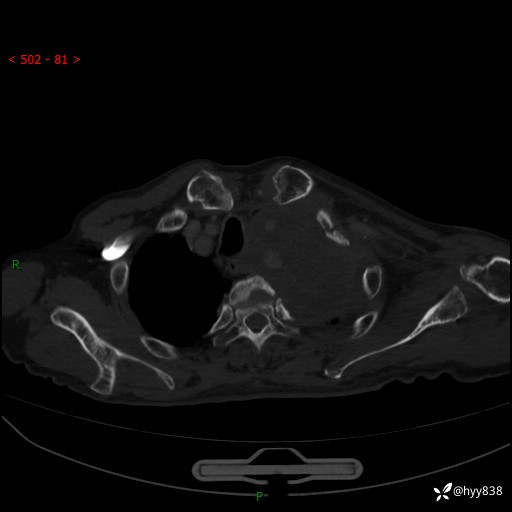

老年男性,气促5月,胸背痛2月。发现肺尖较大肿块,摧枯拉朽之势---结果公布~

现病史:患者于5月前饮酒后突发静息状态下气促不适,无胸闷、胸痛、发热、咳嗽、咳痰等不适,于当地第五人民医院及我院就诊,输液治疗后(具体不详)后气促稍缓解,遂出院后自行口服中草药治疗。近2月出现胸背痛,伴左上肢疼痛、乏力、感觉异常,稍有咳嗽、咳痰,咳黄痰、痰液粘稠,无咳血。为进一步诊治来我院。

胸部CT增强扫描(外院平扫)